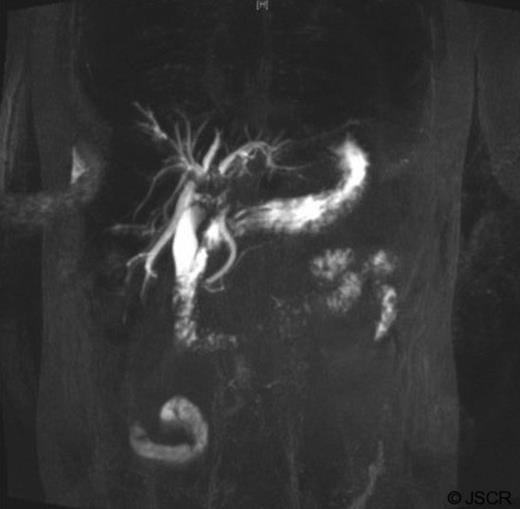

Tumour markers revealed elevated carbohydrate-antigen 19-9 at 807kU/L (normal <40kU/L) suggesting bile-duct disease (1) whilst α-fetoprotein was 4kU/L, within normal range. Magnetic resonance Cholangiopancreatography (MRCP) indicated filling defects in right and left bile ducts (figure 2) and portal vein thrombosis.